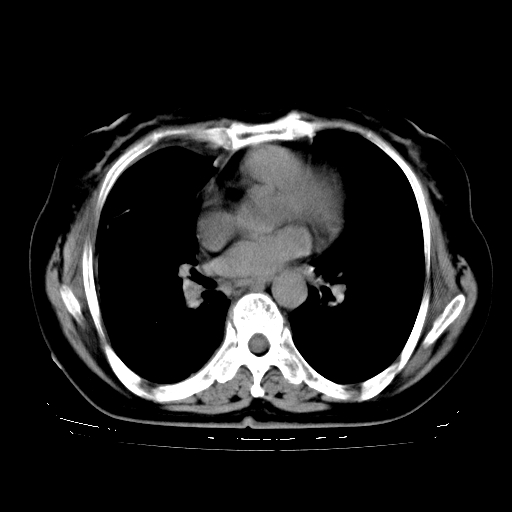

以下是引用zhangzhongshou在2008-3-22 12:52:00的发言:[br]1、右侧液气胸。[br]2、腹水。建议进一步检查。

以下是引用鲁巨ct在2008-3-22 14:10:00的发言:[br]1、右侧液气胸,右中下叶节段性不张。[br]2、腹水,建议上腹部ct检查

以下是引用zjzjr在2008-3-22 17:19:00的发言:[br]1、右侧液气胸,右下叶节段性不张。[br]2、腹水,建议上腹部ct检查